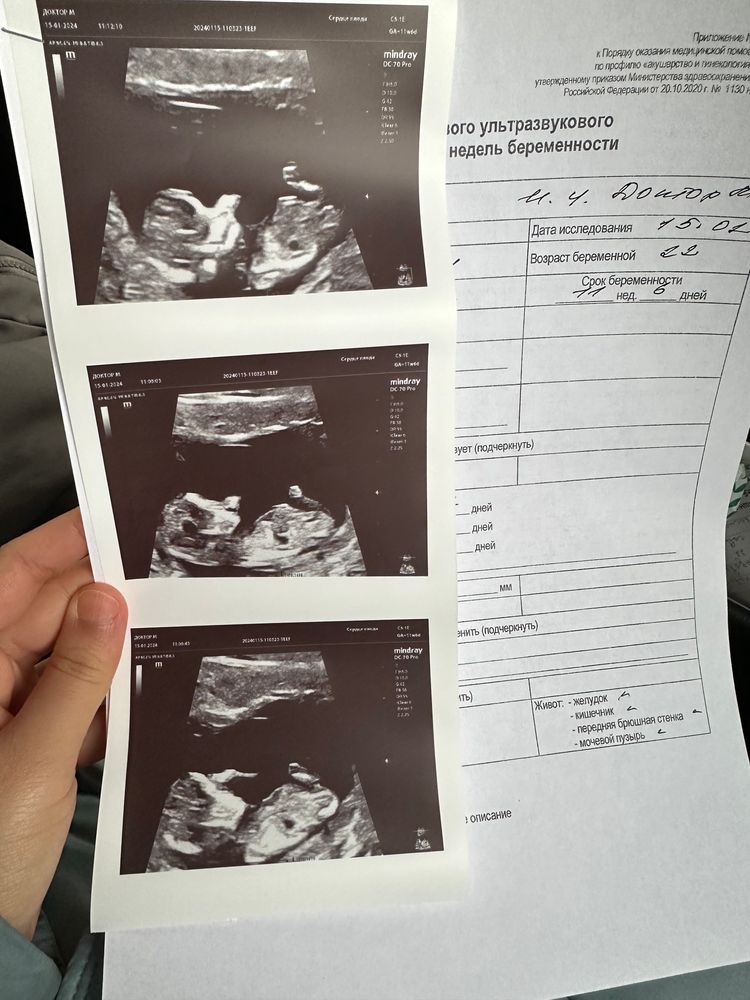

Сегодня был первый скрининг малыша🤍 Это такое неописуемое чувство, когда на экранчике видишь своего кроху🥹 Сердцебиение 168уд. Предположили что будет мальчик, Плод не совпадает со сроком беременности, сказали выглядит больше по сроку, сейчас поставлю снимку узи, может кто-нибудь разберется по снимку мальчик или девочка😅😅 Ну уж не терпится уже узнать пол малыша 😂